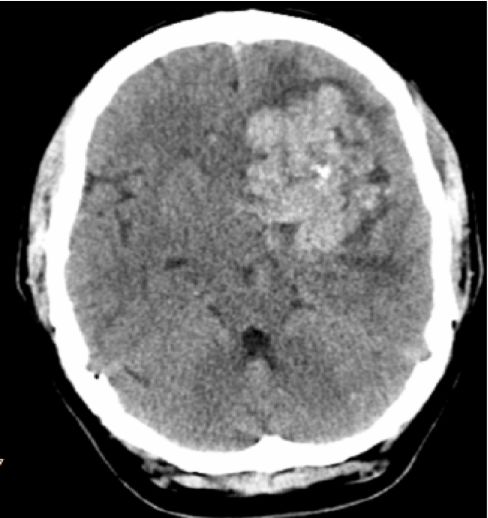

患者一天前因感冒不适伴头晕去当地医院就诊,无头痛、恶心呕吐等症状,也无肢体抽搐等。当地头颅CT检查发现“左额巨大肿瘤”(图1),转至浙江大学医学院附属第二医院。

图1. 头颅CT示病灶呈团块不均匀高密度,内见钙化灶,周围轻度水肿带。